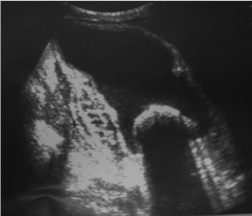

The other basic bioassays were without abnormalities: hemoglobin, platelets, liver enzymes, creatinine, blood glucose, serum calcium, ionogram, muscle enzymes, and serum protein electrophoresis. Chest X-ray and electrocardiogram were normal. The abdominal ultrasound showed the existence at the level of the RIF of an oval formation of 14 cm long axis, with heterogeneous echostructure, fluid center, and a liquid-liquid level. It contained a 4.5 cm diameter hyperechoic, laminated, and mobile arciform image, followed by a posterior shadow cone (Figure 1).

Figure 1. Abdominal ultrasound: heterogeneous mass, with a liquid-liquid level and a hyperechoic, laminated arciform image, followed by a posterior shadow cone